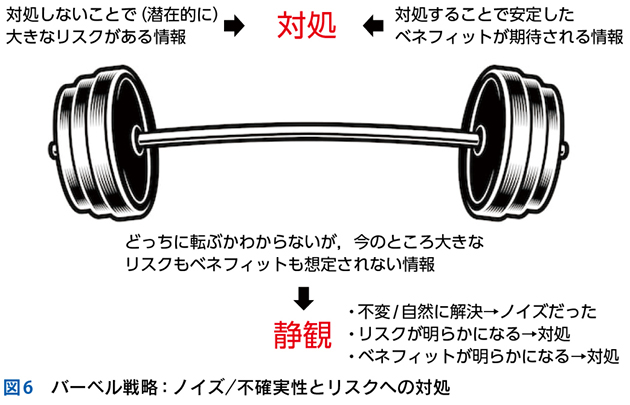

5 ノイズと多元論

▶ ノイズの問題点は,当然のことだが診断を誤った方向に導くことにある。ノイズ情報を含めてフレーミングを行えば(すなわち,ノイズ情報も一元的に説明できるような疾患を探すことにすれば),ノイズの定義からしてフレーム内に真の診断が存在しなくなる。したがって,フレーミングに用いる問題定義からは,ノイズを慎重に排除する必要がある。

▶ ノイズとシグナルを診断前に完全に見わけることは不可能なので,安全なのは一元論(いわゆる「オッカムの剃刀」)に過度にこだわらず,「ノイズであることが否定できない(シグナルであることが確実でない)情報はフレーミングに用いない」あるいは「ノイズであることが否定できない情報を外したバージョンのフレーミングも用意する」という謙虚な態度をとることだろう。

▶ ノイズの可能性がある情報も含めた「全体像」から診断を導くのは直観に任せておいて,分析的診断におけるフレーミングの段階では,早期閉鎖を避けるため,確実にシグナルである少数の情報を軸にしていくべきである。ノイズの可能性がある情報についてはまずは多元論を許容して別個に解釈を行い,結果として一元論に統合されることがある,という接し方がよいだろう。

▶ ノイズを克服するためには,ノイズとシグナルを見わける目や謙虚な推論態度を養うだけでなく,「なるべくノイズを発生させない」情報取得戦略が必要になる。これらについては第4章で詳述する。